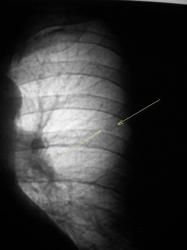

Было высказано предположение о наличии "маленького периферического рака", зафиксирована "линзеподобная тень" паракостально. Пациент направлен на консультацию в онкологический диспансер.

2009 г.

Окружающая легочная ткань - 2008 и 2009 г.

Вердикт диспансера - "наблюдение в динамике".

Кстати, какие-то неясные очажки вокруг. А вдруг туберкулема?